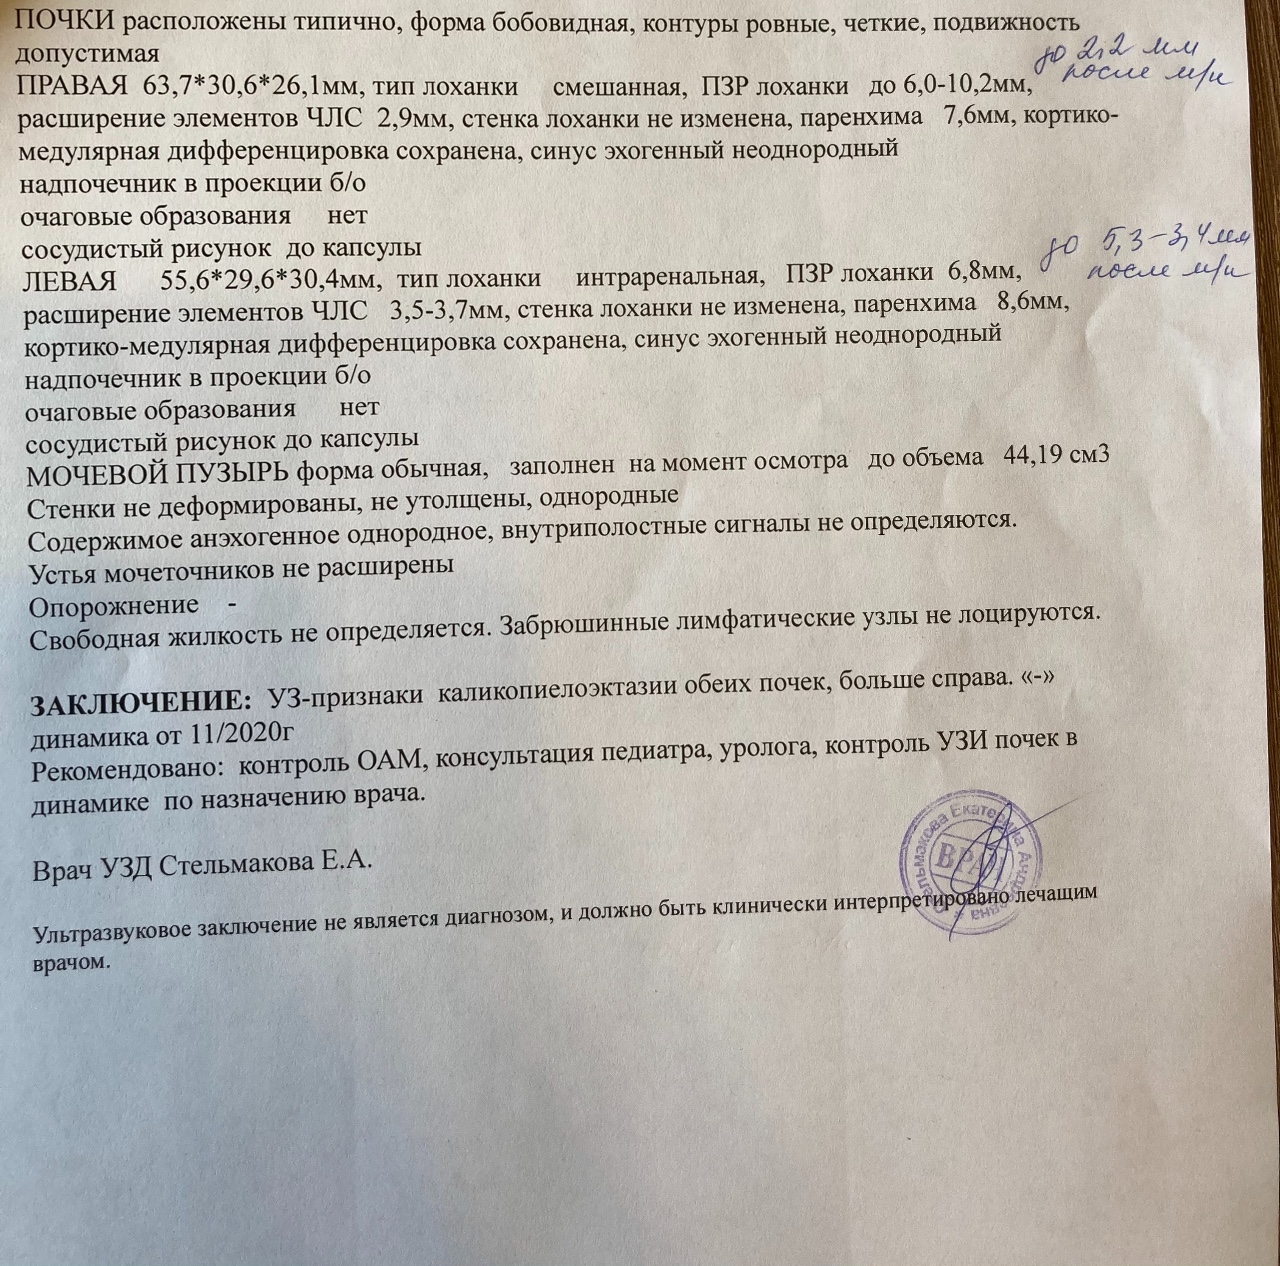

Интраренальная лоханка: рентгеновские снимки и примеры

Раздел: Фотоэссе